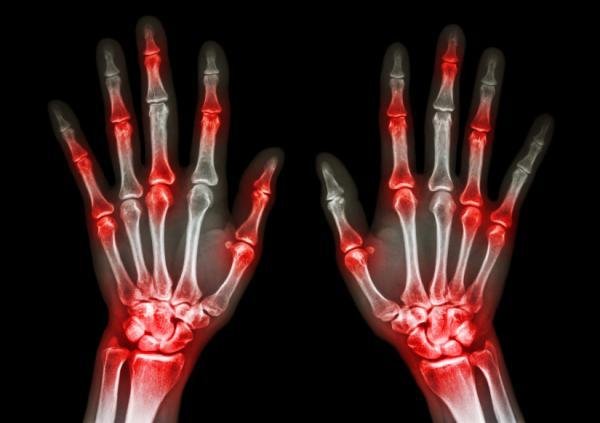

diferenças entre artrose e artriteA artrite reumatoide é uma doença auto-imune que afeta múltiplas articulações num padrão simétrico (nos dois lados do corpo), incluindo habitualmente as das mãos e pés, originando inchaço, dor e muitas vezes levando à destruição definitiva do interior da articulação causando deformidades articulares, especialmente em mãos e dedos, podendo envolver ainda outros tecidos ou órgãos.

Quando a artrite reumatoide irrompe, os sintomas podem incluir fadiga, dores musculares e articulares, e rigidez, principalmente pela manhã e após períodos de inatividade. As articulações, geralmente das mãos, punhos e pés, muitas vezes ficam vermelhas, inchadas, dolorosas e sensíveis.

É comum a artrite reumatoide causar inflamação em diferentes articulações nos dois lados do corpo.

A inflamação crônica pode prejudicar os tecidos do corpo, como cartilagens e ossos, levando à erosão e fraqueza dos ossos e dos músculos e à deformação e destruição da articulação.